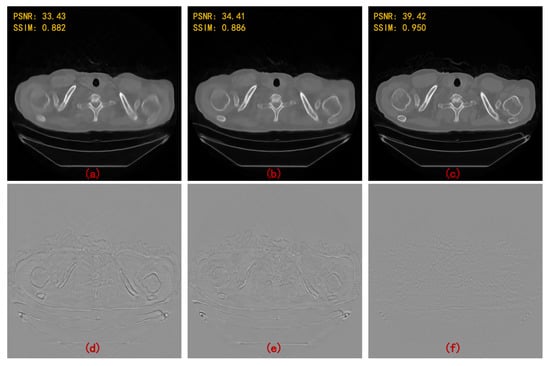

| 90 Views | 60 Views | |||

|---|---|---|---|---|

| PSNR | SSIM | PSNR | SSIM | |

| FBPConvNet [13] | 37.611 | 0.921 | 35.578 | 0.896 |

| RED-CNN [14] | 37.209 | 0.902 | 34.528 | 0.859 |

| DD-Net [22] | 36.380 | 0.912 | 34.424 | 0.892 |

| MWCNN [23] | 38.664 | 0.943 | 36.531 | 0.921 |

| HDNet (WCNN-based) [29] | 34.506 | 0.900 | 32.259 | 0.869 |

| HDNet (Unet-based) [30] | 35.459 | 0.903 | 33.377 | 0.886 |

| HDNet (WUnet-based) | 36.750 | 0.924 | 35.132 | 0.904 |

| HDNet (MWCNN-based) | 40.204 | 0.956 | 37.718 | 0.938 |